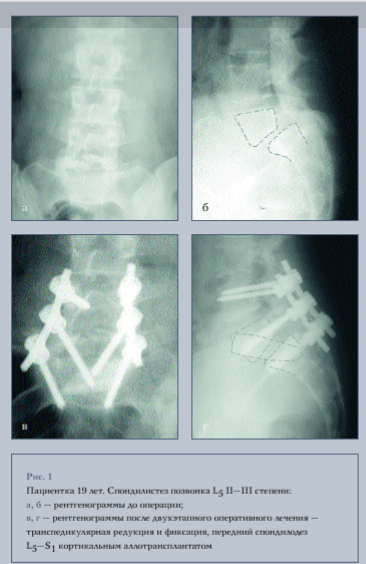

В зависимости от степени смещения по Мейердингу распределение пациентов было следующим: спондилолистез I степени - у двух , II степени - у восьми, III степени - у двенадцати, IV степени - у пяти; у трех пациентов был обнаружен спондилоптоз. Таким образом, смещения I-II степени у 33,3 % больных, тяжелые и крайне тяжелые - у 66,7 %.

В зависимости от уровня фиксации мы разделили больных на 4 группы: больным I группы произведена фиксация двух сегментов, винты вводились в L4, L5 и S1 позвонки (рис. 1); в остальных группах производилась фиксация трех сегментов, при этом во II группе винты вводились в L3, L4, L5 и S1 позвонки, в III - в L3, L5 и S1 позвонки и в IV группе в L3, L4 и S1 позвонки (рис. 2).

Межтеловой спондилодез из переднего внебрюшинного доступа выполняли 22 пациентам, из них 15 - кортикальным аллотрансплантатом, 2 - аутотрансплантатом из гребня подвздошной кости и 5 - комбинацией алло- и аутотрансплантатов. Сроки выполнения второго этапа были различными. Одному пациенту он был выполнен сразу после дорсального вправления и фиксации, остальным - второй этап проводили в различные сроки после первой операции: до одного месяца - 10 пациентам, до трех месяцев - 5, свыше трех месяцев - 5 пациентам.

Всем пациентам с I-II степенями смещения, за исключением одного, производилась фиксация двух сегментов - Ц_5 и L5-S1, т. е. они относились к I группе фиксации. У всех пациентов со спондилолистезом I степени и у двух II степени во время операции было достигнуто полное вправление смещенного позвонка. У остальных пациентов со II степенью смещения осуществлено вправление на 65 %. Угол смещения позвонка (по Митбрейту) уменьшился на 18,1 % от исходной величины. Угол сагиттальной ротации позвонка L5 и величина лордоза в данной группе, кроме одного случая, не изменились.